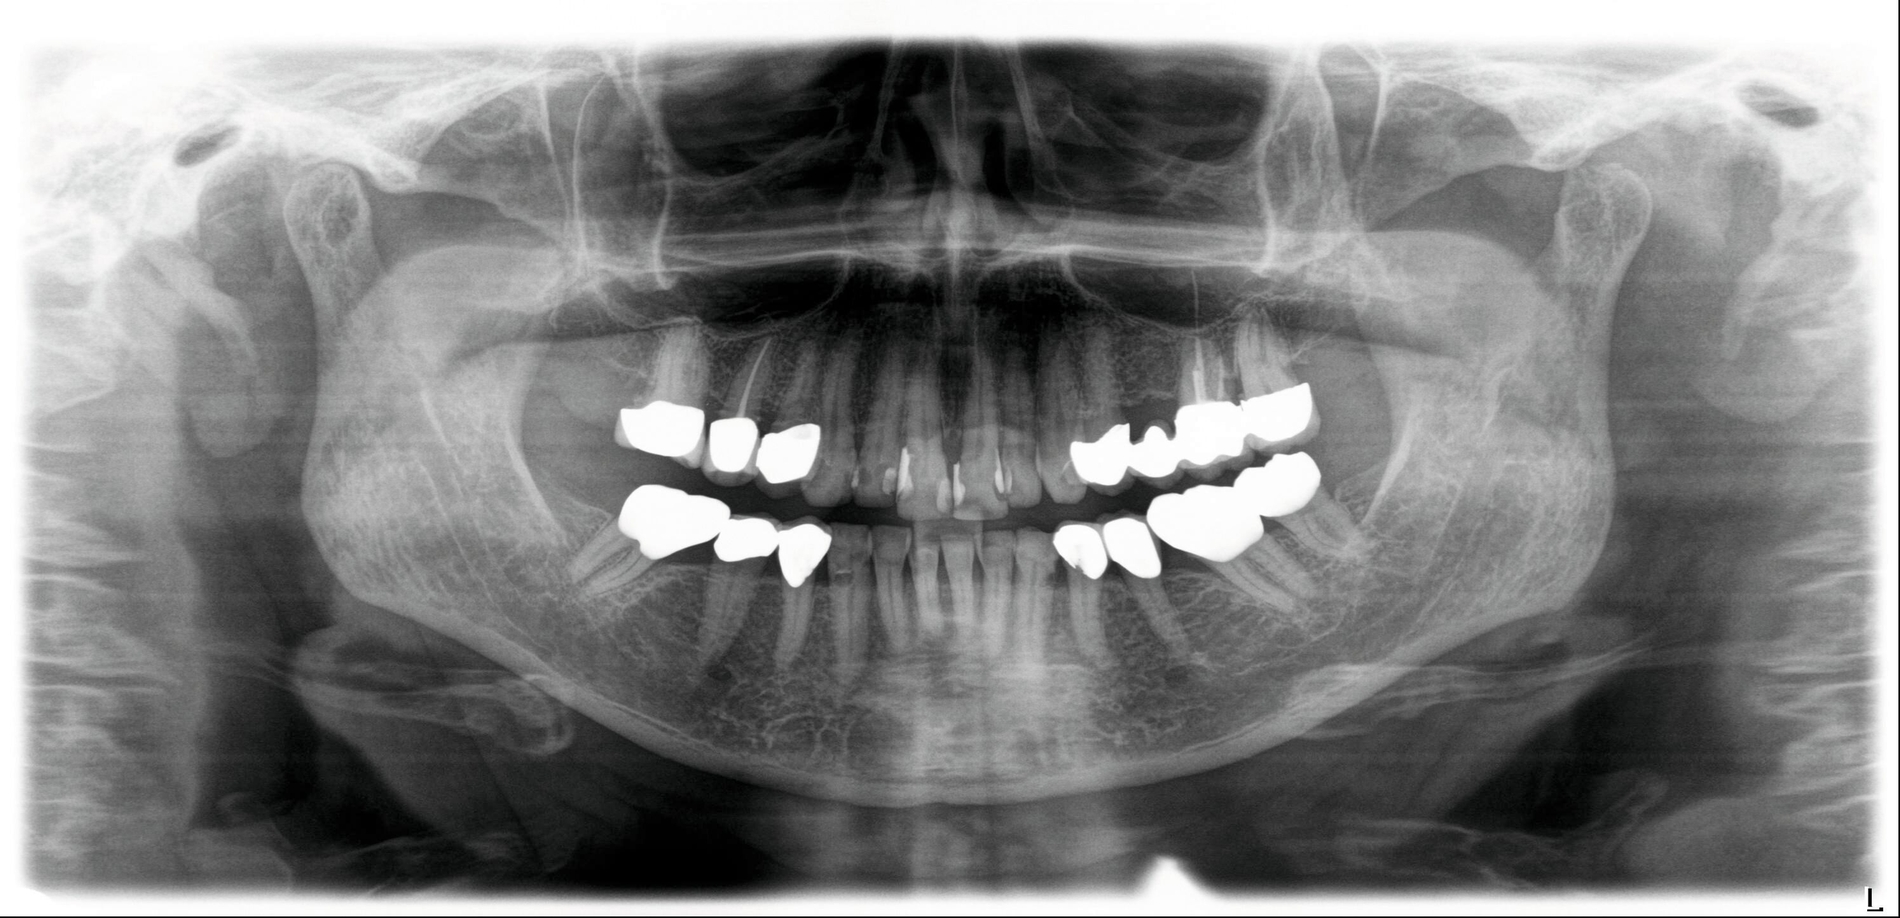

Hier wurde, neben einer klinischen Untersuchung, eine radiologische Diagnostik mittels OPG und DVT durchgeführt (Abbildung 3). Im Ergebnis manifestierte sich der dringende Verdacht, dass die überpresste Wurzelfüllung (Guttapercha-Stift/Sealer) die chronifizierte Pilzinfektion ausgelöst und unterhalten hatte. Daher wurde entschieden, den Zahn 26 zu extrahieren und gleichzeitig das überpresste Wurzelfüllmaterial zu entfernen.

Unter lokaler Anästhesie wurde der Zahn 26 extrahiert. Dabei erfolgte eine alveoläre Osteotomie, um einen suffizienten Zugang zur Kieferhöhle zu schaffen und den Guttapercha-Stift/Sealer zu entfernen. Es zeigte sich ein pilzartiger Befall des Wurzelfüllmaterials. Mikrobiologische und histopathologische Präparate wurden eingesendet. Bei dem Kieferhöhlenempyem wurde zur Spülung eine Easy-flow-Drainage eingelegt. Die mikrobiologische und die histopathologische Untersuchung bestätigten den Befall mit Aspergillus fumigatus.

Unstrittig ist seit Langem, dass wurzelkanalbehandelte Zähne mit überpresstem Wurzelkanalfüllmaterial in den Sinus maxillaris einer der Hauptgründe für eine Aspergillose bei immunkompetenten Patienten sind [Beck-Mannagetta et al., 1984]. Wenn der Sealer und/oder die Guttapercha in das periapikale Gewebe extendiert werden, kommt es häufig zu einer entzündlichen Reaktion [Ricucci, 1998].

Ein Aspergillom des Oberkiefersinus kann sich bei immunkompetenten Patienten symptomatisch zeigen, aber auch klinisch asymptomatisch bleiben. Symptomatische Patienten zeigen klassische Symptome einer chronischen Sinusitis mit Nasensekretionen, Schmerzen und manchmal Schwellungen im Bereich des Jochbeins. Oft wird die Diagnose bei asymptomatischen Formen als Zufallsbefund bei der Anfertigung einer Orthopantomografie gestellt, die während einer routinemäßigen zahnärztlichen Behandlung durchgeführt wird [Costa et al., 2007]. Die charakteristische Darstellung im Röntgenbild umfasst typischerweise heterogene Opazitäten, die mit einem metalldichten Fleck im betroffenen Kieferhöhlensinus verbunden sind [Dhong et al., 2000].